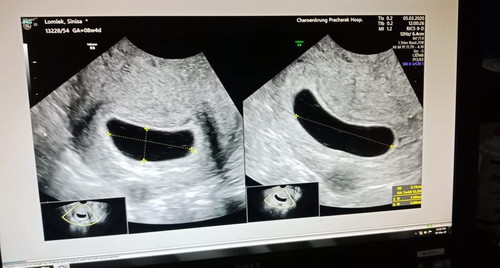

8 wk 4 day ไม่เจอไข่แดง ไม่เจอตัวน้อง แม่ ๆ เจอน้องกันตอนไหนเอ่ย

ซาวด์ตอน9วีค แต่ถุงตั้งครรภ์ขนาดแค่5วีคเองค่ะ ไม่เจอตัวน้องไม่เจอไข่แดงเหมือนกัน แต่ของคุณแม่ถุงตั้งครรภ์ยังโตเท่าอายุครรภ์ก็น่าจะมีสิทธิ์ลุ้นอยู่นะคะ ขอให้โชคดีค่ะ

8 w (ถ้าตั้งท้องปกติ) นี่เจอถุง เจอน้องล่ะค่ะ ฟังเสียงหัวใจเต้นได้แล้ว ของเราอัลตราซาวน์ครั้งแรกตอน 8 w 1 d เจอถุง เจอตัวอ่อน วัดความยาวได้ 1.64 cm หัวใจเต้น 164 ครั้งต่อนาที